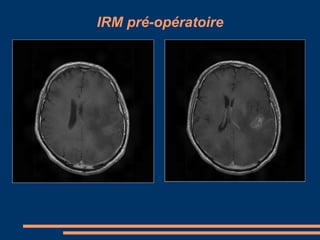

CAS CLINIQUES –GIESSEN+CHU FORT de FRANCE Patient de  35  ans  (GIESSEN) Ralentissement  psychomoteur depuis 1 mois , déficit moteur de l’hémicorps droit d’installation progressive , aphasie  de Wernicke et Broca. Juin 2009 : réalisation d’une IRM cérébrale montrant un glioblastome temporal profond gauche avec effet  de masse. Opéré avec GLIOLAN couplé au Pentero avec option fluoroscopie.

IRM pré-opératoire

IRM pré-opératoire (suite)